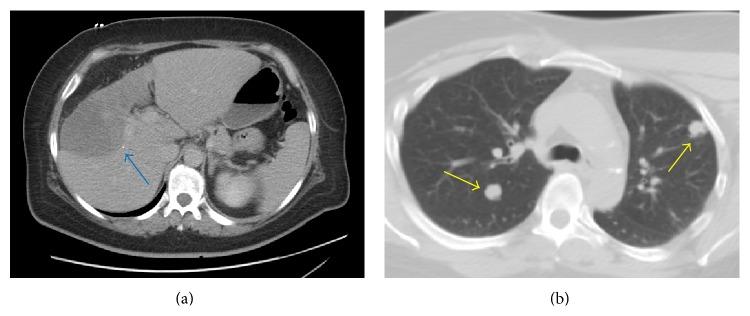

Hepatic epithelioid hemangioendothelioma (HEH) is extremely rare, occurring in 1 to 2 per 100,000, with chemotherapy options not well defined. Our case involved a 49-year-old female who had hepatic masses and metastasis to the lungs with a liver biopsy revealing HEH. After developing a rash from sorafenib, thalidomide was started with the progression of disease stabilized. Resection is only an option in 10% of the cases; therefore, chemotherapy is the only line of treatment. Newer chemotherapy alternatives are targeting angiogenesis via the vascular endothelial growth factor. Thalidomide was first used as an antiemetic, but, sadly, soon linked to phocomelia birth defects. Given the mechanism of action against angiogenesis, thalidomide has a valid role in vascular tumors. In conclusion, the use of thalidomide as chemotherapy is novel and promising, especially in the setting of a rare vascular liver tumor such as HEH.

肝上皮样血管内皮瘤(HEH)极为罕见,发病率为十万分之一至二,化疗方案尚不明确。我们的病例是一位49岁女性,有肝脏肿块并伴有肺转移,肝脏活检显示为HEH。在使用索拉非尼后出现皮疹后,开始使用沙利度胺,疾病进展得以稳定。仅10%的病例可选择手术切除;因此,化疗是唯一的治疗方法。新型化疗药物通过血管内皮生长因子靶向血管生成。沙利度胺最初用作止吐药,但遗憾的是,很快就与短肢畸形出生缺陷有关。鉴于其抗血管生成的作用机制,沙利度胺在血管肿瘤中具有一定作用。总之,将沙利度胺用作化疗药物是新颖且有前景的,尤其是在治疗像HEH这样罕见的肝脏血管肿瘤时。